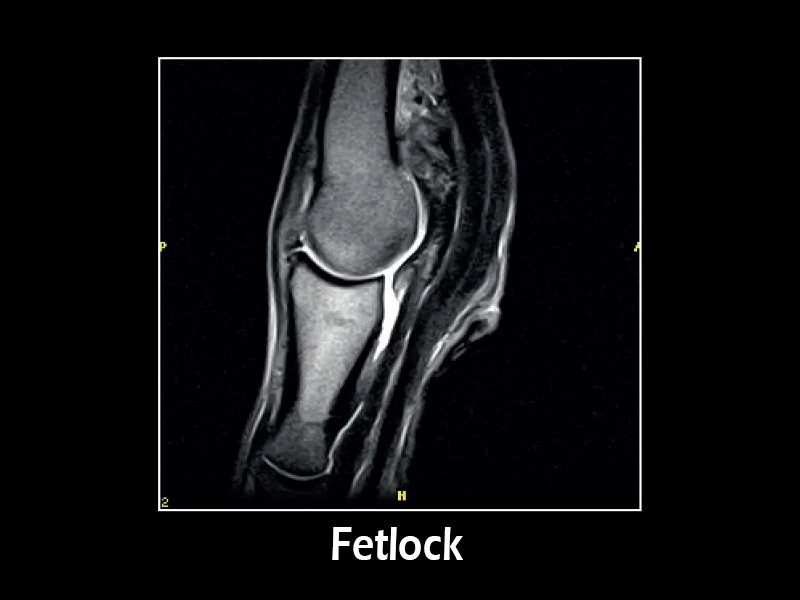

G-scan equine - Nodello 02

G-scan equine - Nodello 01